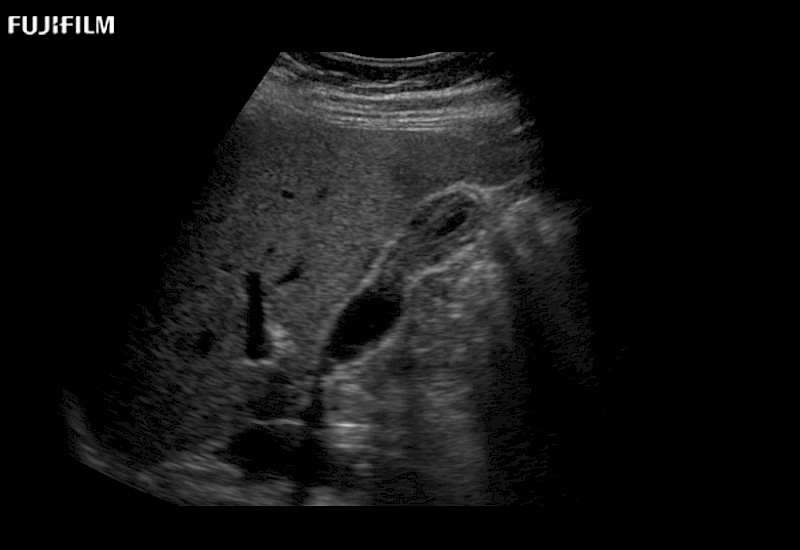

Learn moreFujifilm Healthcare continues to listen to the experts, our neurosurgeons, by developing an ultrasound system specifically designed for the Operating Room.

Guidance is the fundamental purpose for all of our surgical ultrasound technology. Fujifilm Healthcare is committed to designing tools that help neurosurgeons navigate inside the human body and provide the necessary information to immediately make critical surgical decisions.

With the ARIETTA Precision the next level of surgical ultrasound is here.